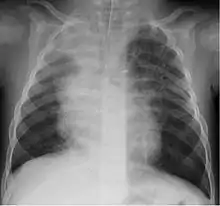

A study in Jordan found that 9% of 220 children hospitalised with lower respiratory tract infection were infected with bocavirus.[30] Of those infected the median age was 4 months. Coughing (100%), wheezing (82.7%) and fever (68.2%) were the most common clinical findings with bronchopneumonia (35%) and bronchiolitis (30%) being the most common ultimate diagnoses.

Although most cases are mild, severe respiratory disease has also been reported.[31]

Life-threatening infection caused by human bocavirus was described in previously healthy 20-months old prematurely born child.[32]